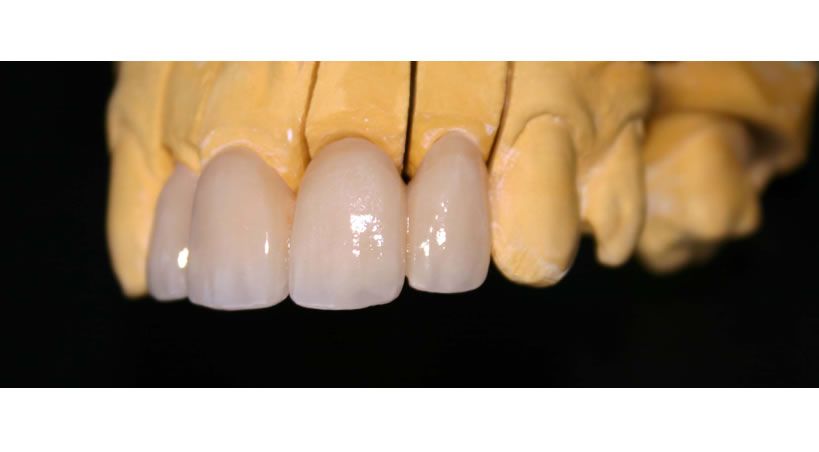

Manejo Protésico de un paciente con hemimandibulectomía

utilizando un plano protésico guía con rampa acrílica: informe de un caso